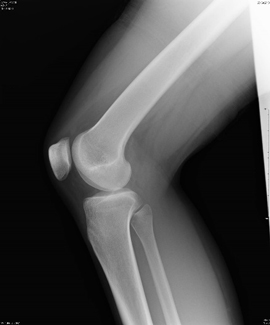

X線撮影では、骨折や結石、体の中に水がたまっている様子などが簡単かつ短時間で確認することが出来るので、放射線部門の中では一番多く撮影される検査です。